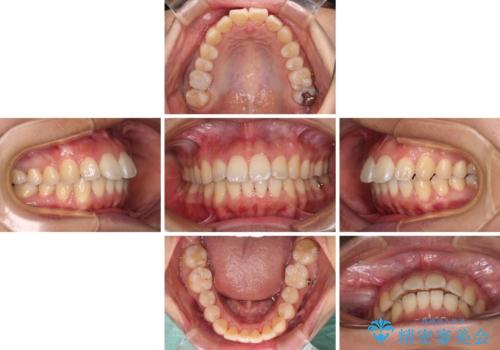

前に出ている前歯を引っ込めたい インビザライン矯正

- 前方に傾斜した上下の前歯を気にして来院された患者様です。

唇の閉じにくさや横顔のシルエットが気になるような突出感ではなかったため、インビザラインを用いて、歯列の遠心移動とIPR(歯と歯の間を削る)により前歯の傾斜を改善していくこととしました。

スムーズに終了すると思われましたが、インビザライン矯正独特の奥歯が咬み合わない状態が続き、更には遠方へ転居されたこともあり、治療期間は長引いてしまいました。